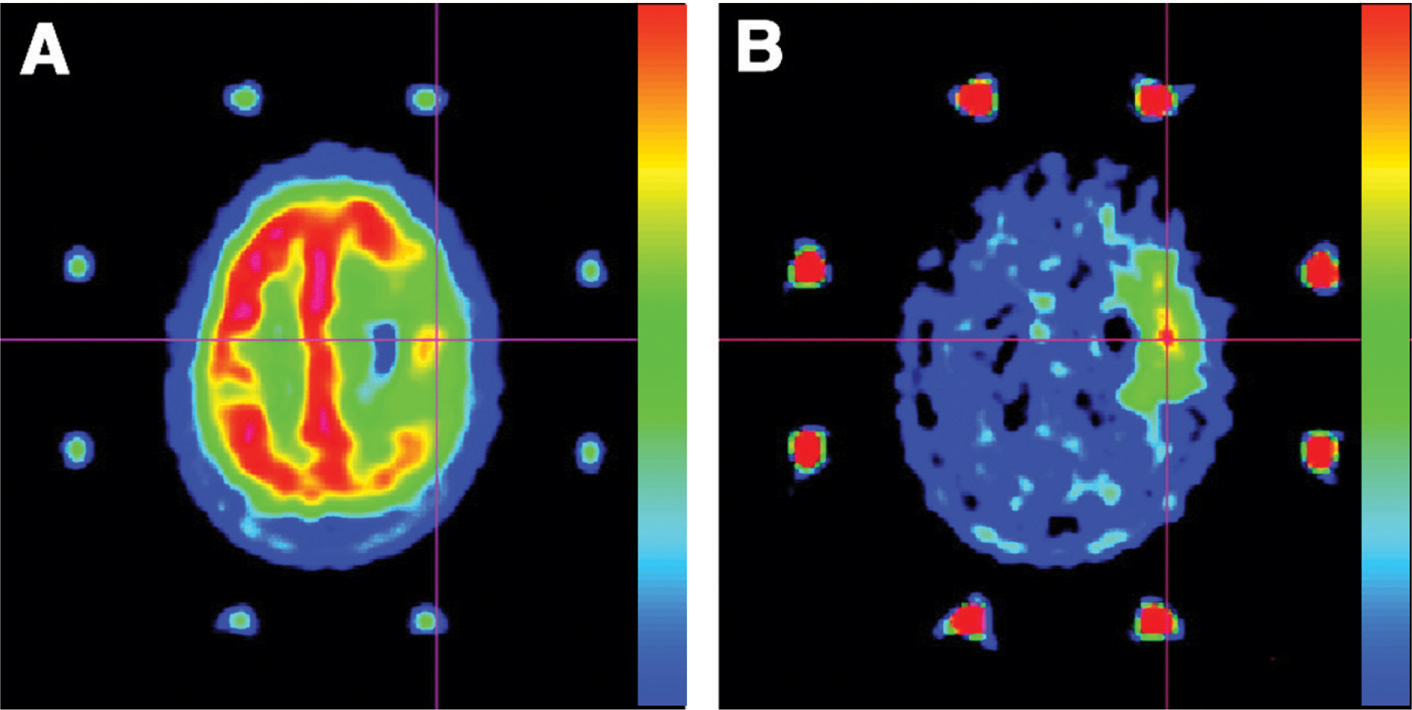

PET enables better identification of intra-tumor heterogeneity compared with standard MRI in addition to delineating tumor extent with much greater accuracy. The identification of malignant foci, commonly defined as “hot spots” in heterogeneous gliomas and a specific characteristic of glioblastomas (58), is essential for biopsy planning. The objective is to ensure that the most biologically aggressive portion of the tumor, which ultimately determines the patient’s prognosis as well as treatment, is not under-sampled (56, 59). Similar to the delineation of tumor extent, amino acid tracers are more suitable than 18F-FDG in identifying malignant foci in gliomas. In a study aimed at guiding stereotactic brain biopsy of gliomas by using 18F-FDG and 11C-MET, the authors showed that all 32 gliomas, 10 of which were glioblastomas, exhibited an area of abnormal 11C-MET uptake, whereas only 7 glioblastomas showed abnormal 18F-FDG uptake (60). An example of superiority of 11C-MET in comparison to 18F-FDG is given in Figure 2. In another study aimed at comparing performances with MRI, stereotactic PET-guided biopsies were also performed with 18F-FDOPA PET. Thirteen of the 16 high-grade biopsy specimens were obtained from regions of elevated 18F-FDOPA uptake, while MRI contrast enhancement was present in only 6 of the aforementioned 16 samples (56). These observations, in accordance with previous results, thus underscore the potential benefit of using PET amino acid tracers in determining the most aggressive portion of the tumor.

Fig 2

Figure 2 PET performed with 18F-FDG (A) and 11C-MET (B) in a 62-year-old woman with a glioblastoma in the left prerolandic cortical area. Uptake of 18F-FDG was reduced in the tumor area except for one area of uptake equivalent to that in the surrounding gray matter. Uptake of 11C-MET was higher in the tumor than in the surrounding cortex, allowing the definition of a target for biopsy. When PET images obtained with the two tracers were co-recorded, the highest focus of 11C-MET uptake corresponded to the hot spot of 18F-FDG uptake (intersecting lines). (Adapted from J Nucl Med 2004;45:1293–1298. Copyright: The Society of Nuclear Medicine and Molecular Imaging, Inc. Reproduced with Permission.)